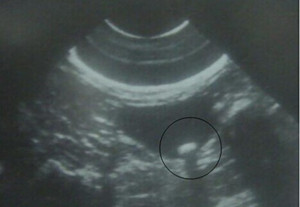

B超检查